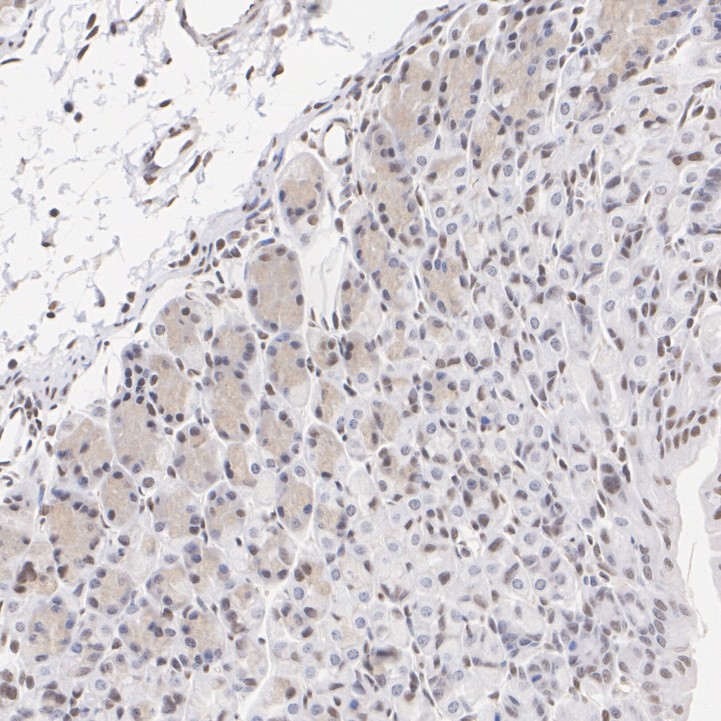

Immunohistochemical analysis of paraffin-embedded human breast carcinoma tissue with Rabbit anti-TAZ / WWTR1 antibody (HA751569) at 1/200 dilution.

The section was pre-treated using heat mediated antigen retrieval with Tris-EDTA buffer (pH 9.0) for 20 minutes. The tissues were blocked in 1% BSA for 20 minutes at room temperature, washed with ddH2O and PBS, and then probed with the primary antibody (HA751569) at 1/200 dilution for 1 hour at room temperature. The detection was performed using an HRP conjugated compact polymer system. DAB was used as the chromogen. Tissues were counterstained with hematoxylin and mounted with DPX.